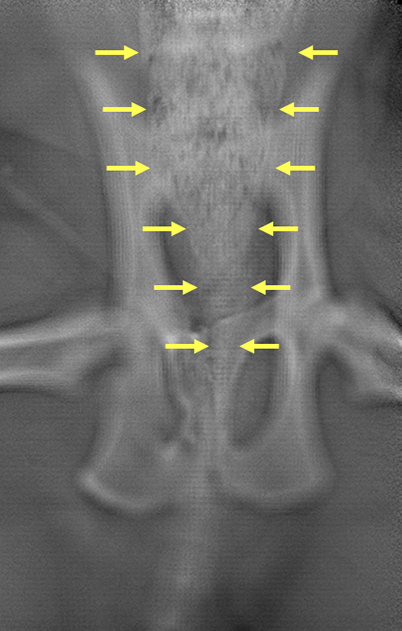

Figure 2. Lateral and ventrodorsal radiographic projections of the pelvis demonstrating malunion of the right ischium and pubis.

Radiography of the abdomen (Figure 1) revealed a full and severely distended colon. The seventh lumbar vertebra measured 17mm and the colon at its widest part measured 30mm, confirming megacolon. Views of the pelvis (Figure 2) revealed deformities consistent with malunion of the right ischium caudal to the acetabulum and of the pubis on the right side. The sacral index measured 71%, suggesting a low risk of constipation.